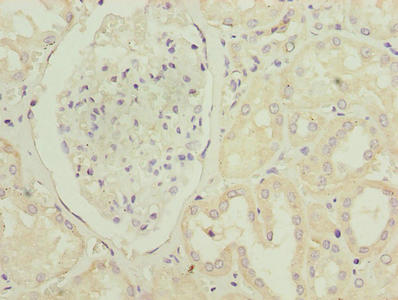

Immunohistochemistry of paraffin-embedded human kidney tissue using CSB-PA018946LA01HU at dilution of 1:100